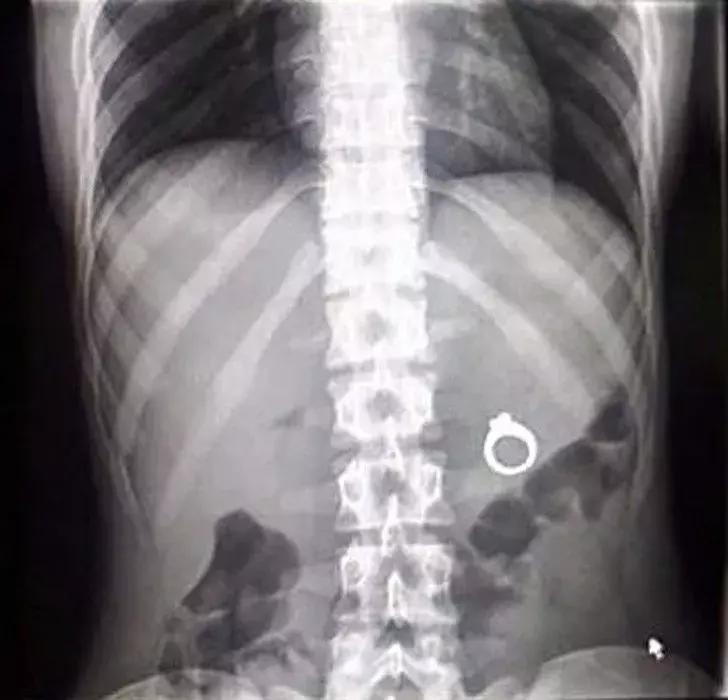

婚戒就应该在手指上,怎么到肚子里了